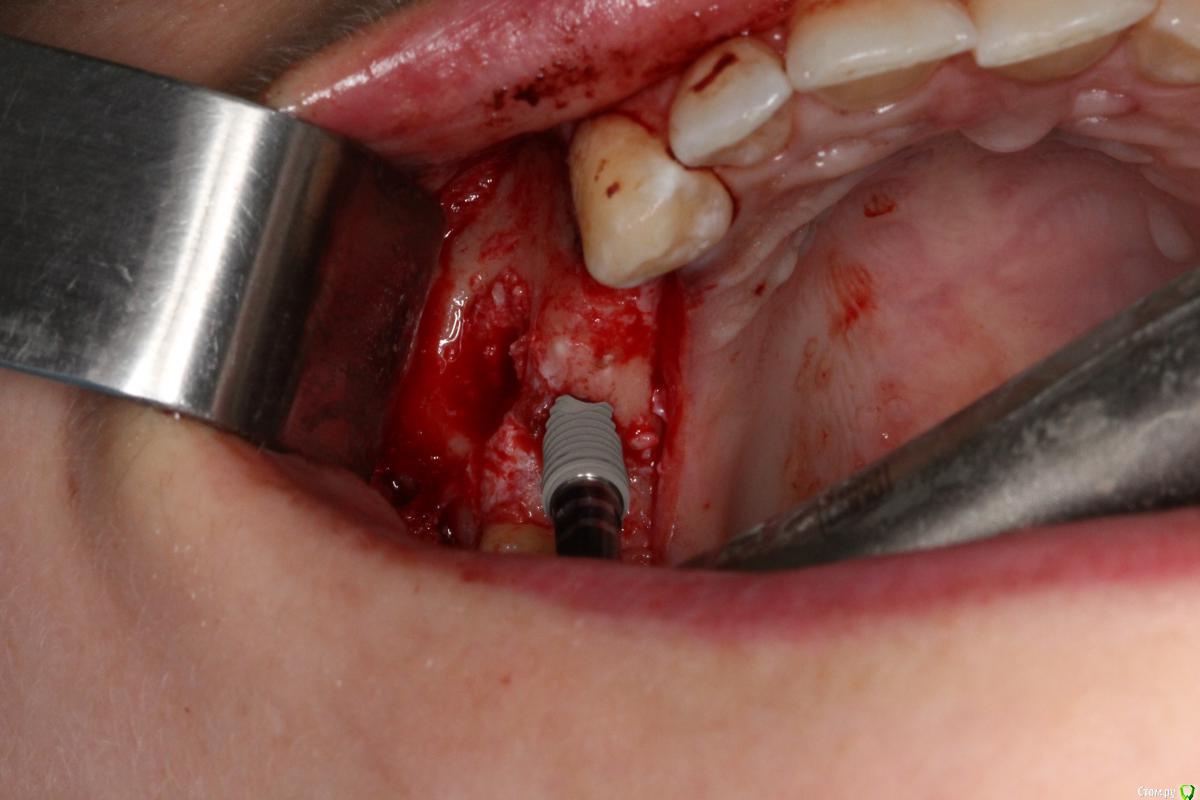

Robinbobin Опубликовано 25 марта, 2015 Поделиться Опубликовано 25 марта, 2015 Имплантаты Dio UF ll,костный материал ауто+остеоматрикс.Хотелось бы услышать мои ошибки 6 Ссылка на комментарий

red_butler Опубликовано 25 марта, 2015 Поделиться Опубликовано 25 марта, 2015 Robinbobin а зачем 1.4 так заглубили? Я бы плюсом сделал НКР на оба винта Ссылка на комментарий

Robinbobin Опубликовано 25 марта, 2015 Автор Поделиться Опубликовано 25 марта, 2015 Robinbobin а зачем 1.4 так заглубили? Я бы плюсом сделал НКР на оба винта Читал что шурупы конусные нужно заглублять,а нкр зачем?дефицита кости с вестибулярной стороны нету же вроде 1 Ссылка на комментарий

колесников Опубликовано 25 марта, 2015 Поделиться Опубликовано 25 марта, 2015 Вестибулярная компактная пластинка резорбируется на 3 мм у шеек имплантов. Вы конечно оставили дополнительно остеоматрикс вестибулярно ? В области 14 обязательно подсадите стт, можно на этапе формирователя. 16 можно было и короче взять,тогда бы он целиком находился в материале. А в целом Всё достойно. Ссылка на комментарий

Robinbobin Опубликовано 25 марта, 2015 Автор Поделиться Опубликовано 25 марта, 2015 Вестибулярная компактная пластинка резорбируется на 3 мм у шеек имплантов. Вы конечно оставили дополнительно остеоматрикс вестибулярно ? В области 14 обязательно подсадите стт, можно на этапе формирователя. 16 можно было и короче взять,тогда бы он целиком находился в материале. А в целом Всё достойно. Ассистент не сфографировал момент подсадки сст в область имплантата 1.4 поэтому наверно и забыл написать))) но на этапе формирователя думаю еще подсадить Спасибо! Ссылка на комментарий